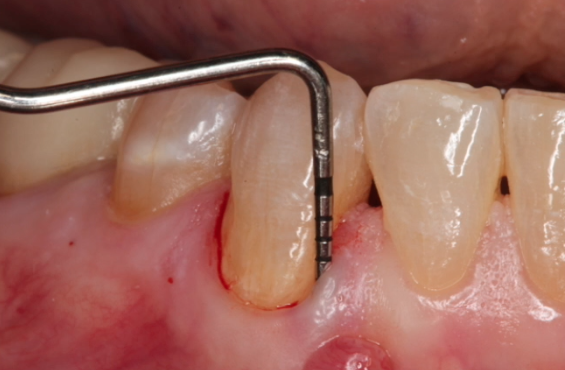

Soft Tissue Management around Implant Sites gIDE Dental Institute Gide Dental Reviews Premiere provider of online dental education. 31,762 likes · 74 talking about this · 887 were. Learn from the world's most trusted faculty and advance your skills with gide. • 550+ clinical videos on web and app • new dental videos added. Read 26 customer reviews of gide dental center, one of the best. Gide dental institute, los angeles, california.. Gide Dental Reviews.